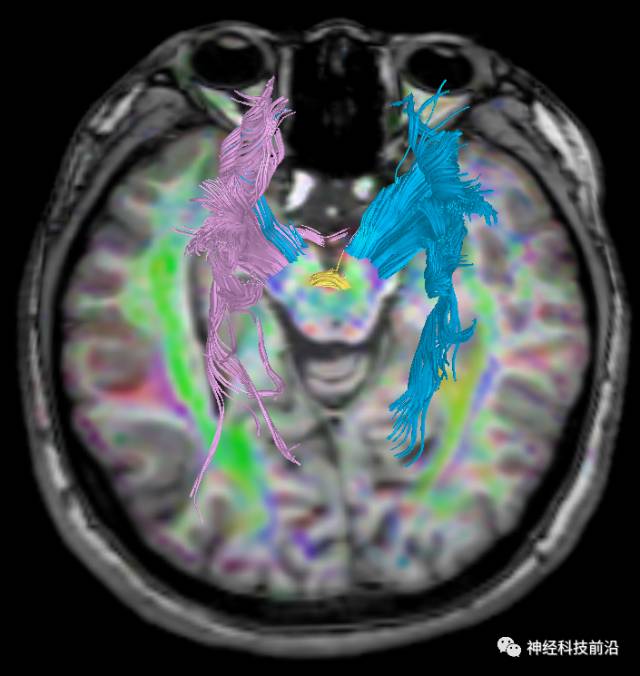

皮质脊髓束与皮质脑桥束的关系毗邻

终上所述:脑干高信号为一近环形纤维束,内囊后肢高信号为皮质脑桥束,皮质脊髓束在中脑位置略靠后。高信号位于中脑前缘,是皮质脑桥束的位置所在,另外有部分桥连纤维。